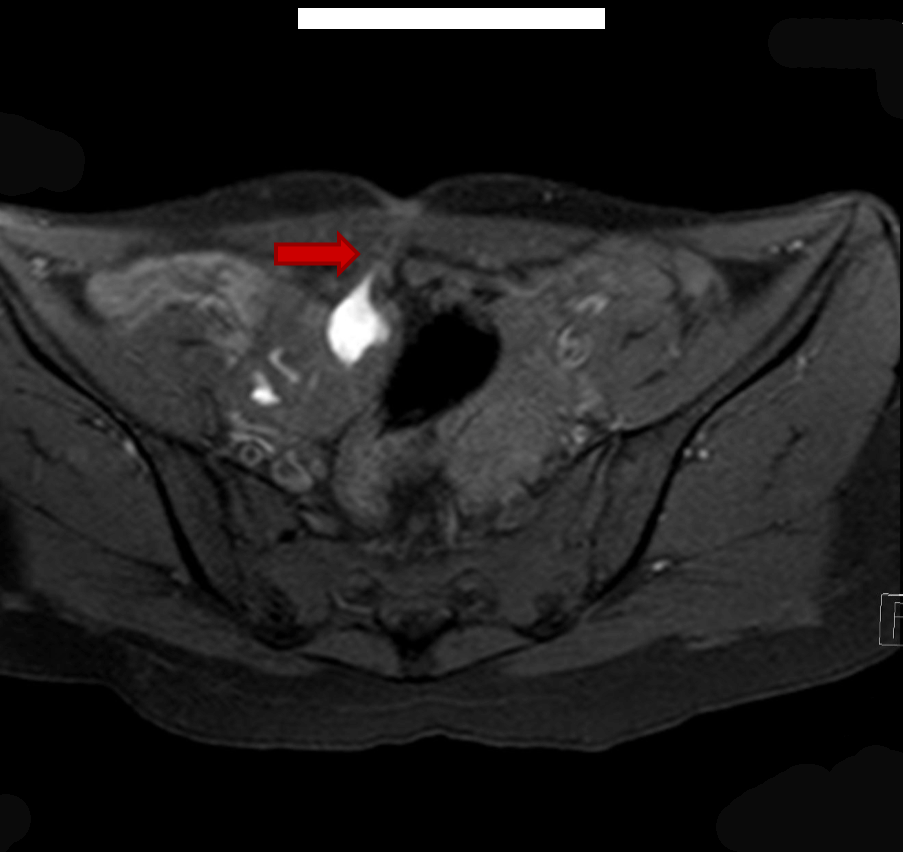

On local examination pubic hair were present, Tanner stage V. On speculum examination cervix was normal but deviated to left. On bimanual examination same mass was felt from right fornix and small size uterus from left fornix. Ultrasonography revealed bicornuate uterus with collection within endometrial cavity of right horn likely non-communicating. Bulky right ovary with a tract noted from it to the scar site on anterior abdominal wall likely scar endometriosis with solitary left kidney. Magnetic resonance imaging scan revealed two uterine cavities with a single cervix and vagina and a left communicating horn and a right non-communicating uterine horn with hematometra and right hematosalpinx (Figure 2). Blood filled tract was extending from the hematosalpinx to the skin opening on the anterior abdominal wall (Figure 3). Patient and her family were counseled and prognosticated about poor fertility potential. She was given the option of excision of the horn. Patient wished to retain her menstrual and child bearing function. She was taken up for laparotomy. Intra operatively fistulous tract was delineated with a probe (Figure 4) and a hypoplastic communicating uterine horn was identified. A right non-communicating normal sized uterus was present.

Figure 3: T1WI FS axial magnetic resonance imaging scan showing blood filled tract from right hematosalpinx to cutaneous opening in anterior abdominal wall.